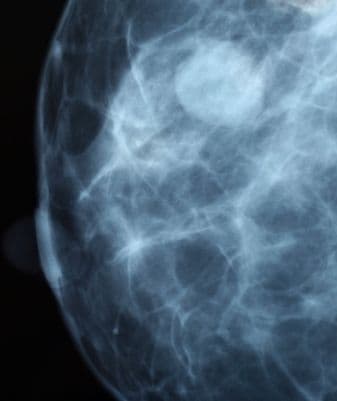

A mellrák műtét utáni rekonstrukció